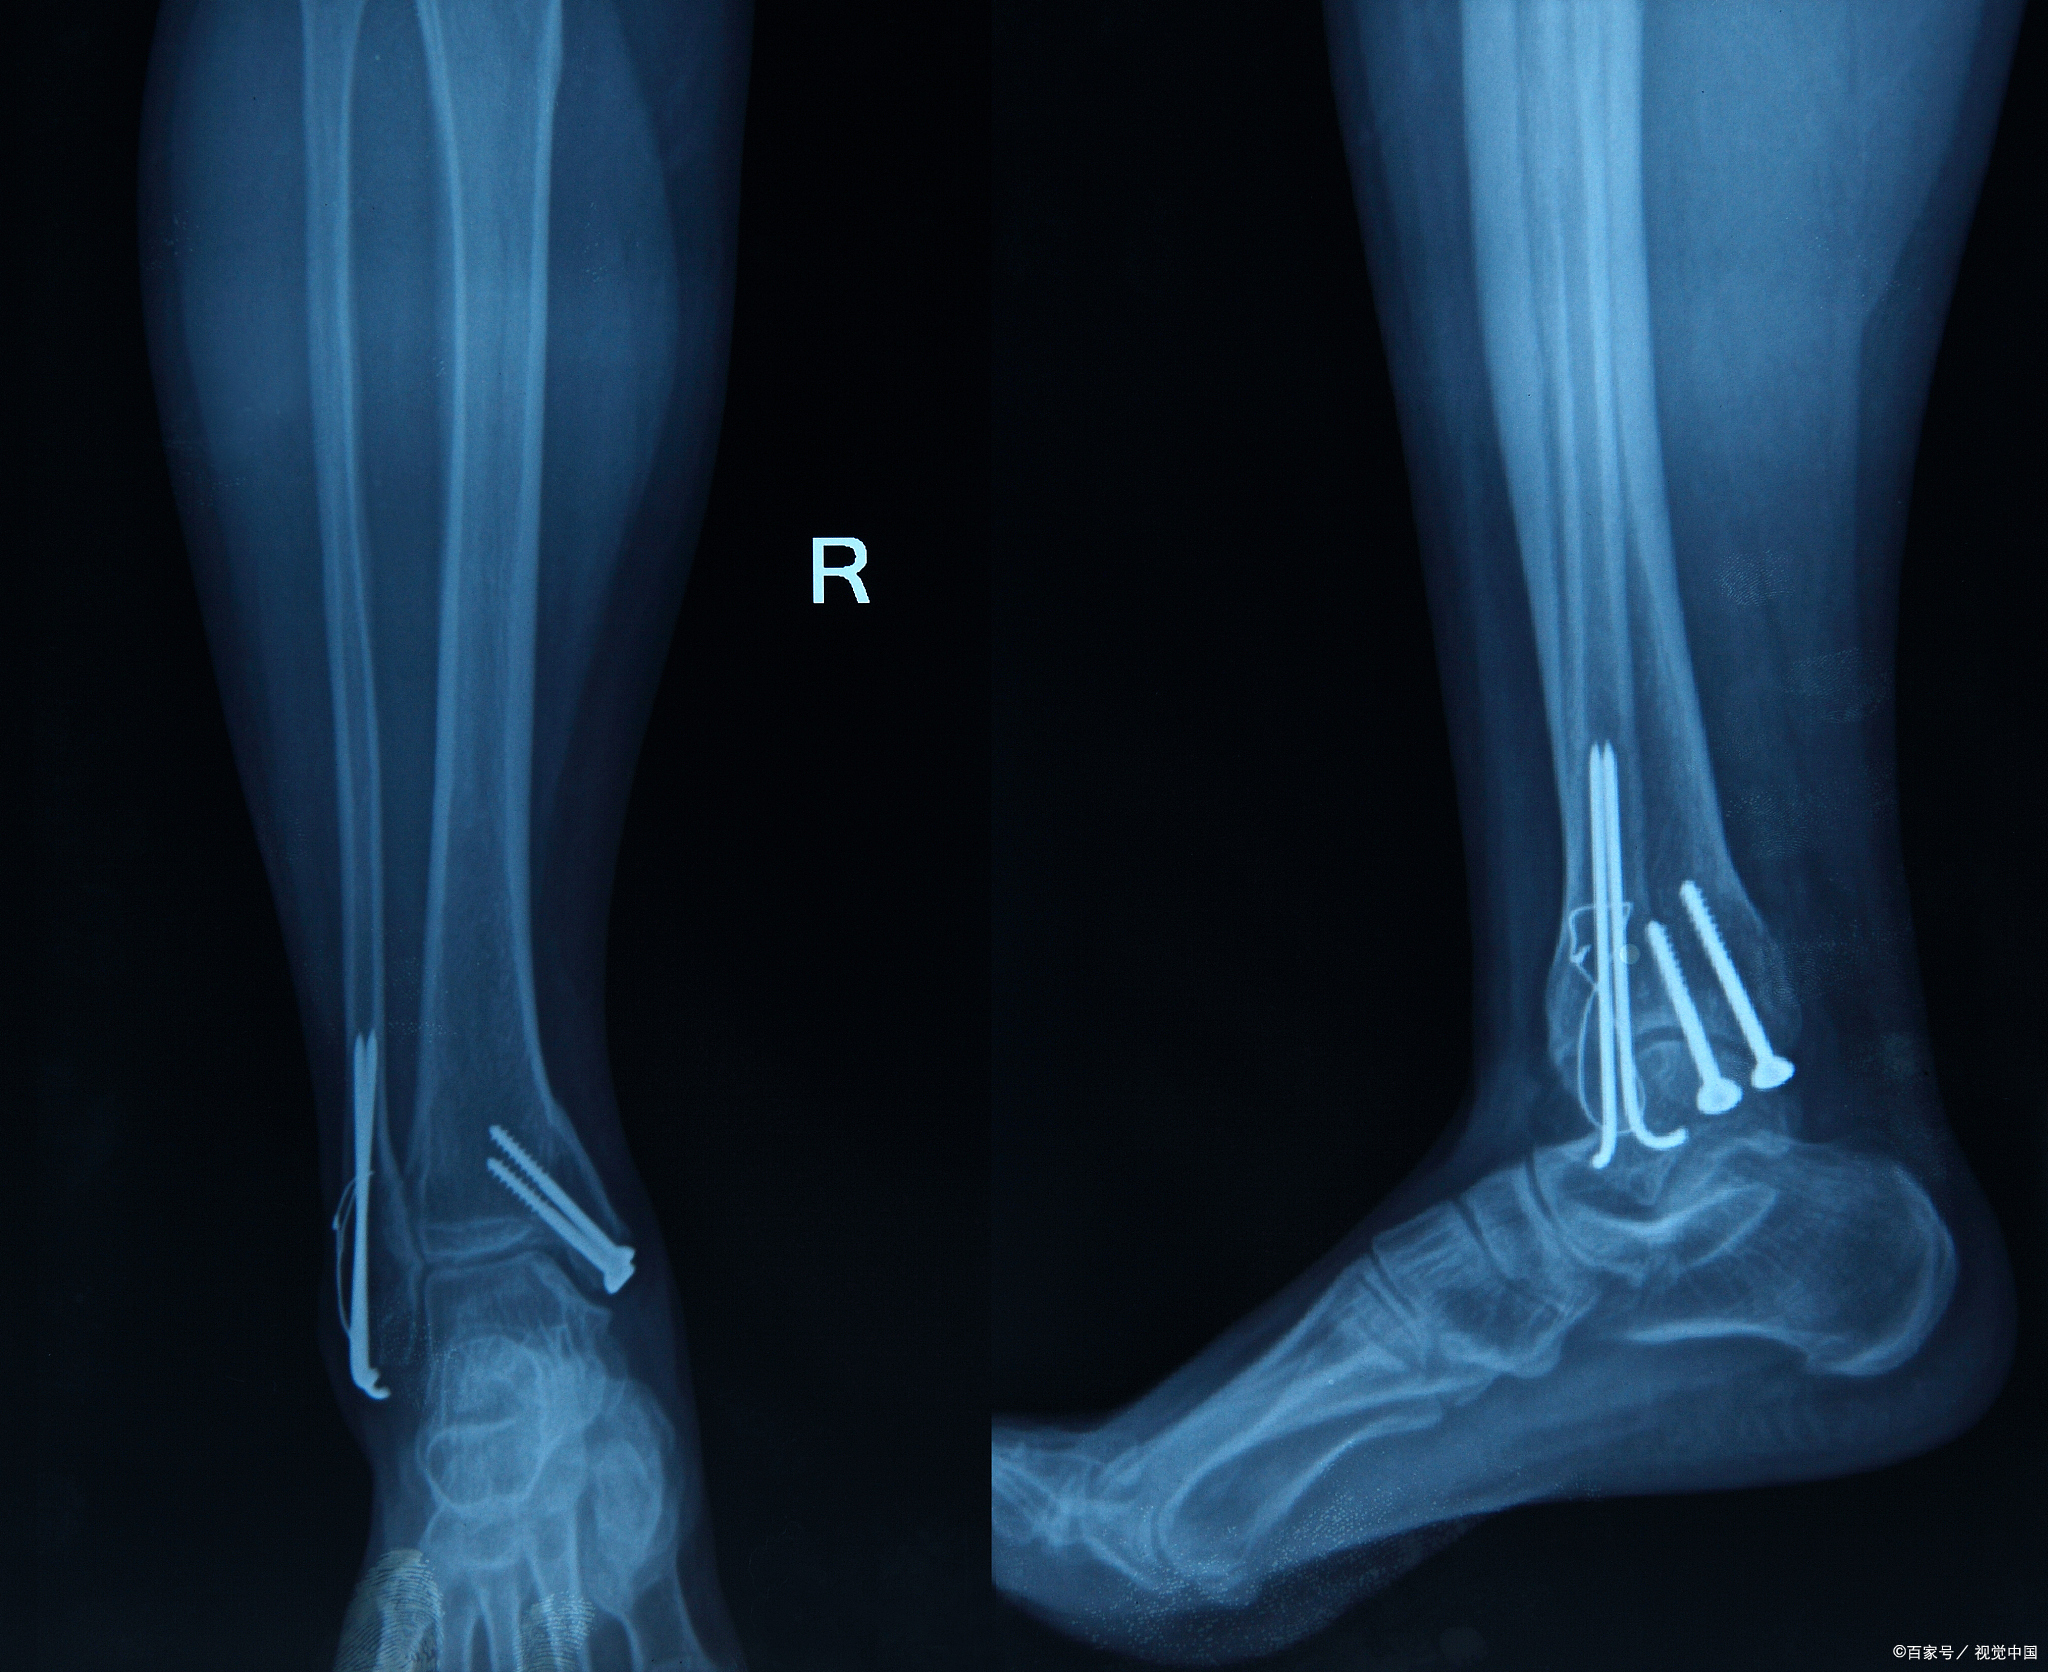

股骨头坏死的症状有哪些(股骨头坏死的典型症状表现)

平时上街的时候经常会看到有人走路会跛行,有很多的原因都会导致跛行的产生。但是你可知道股骨头坏死也是导致跛行产生的一种原因吗?...